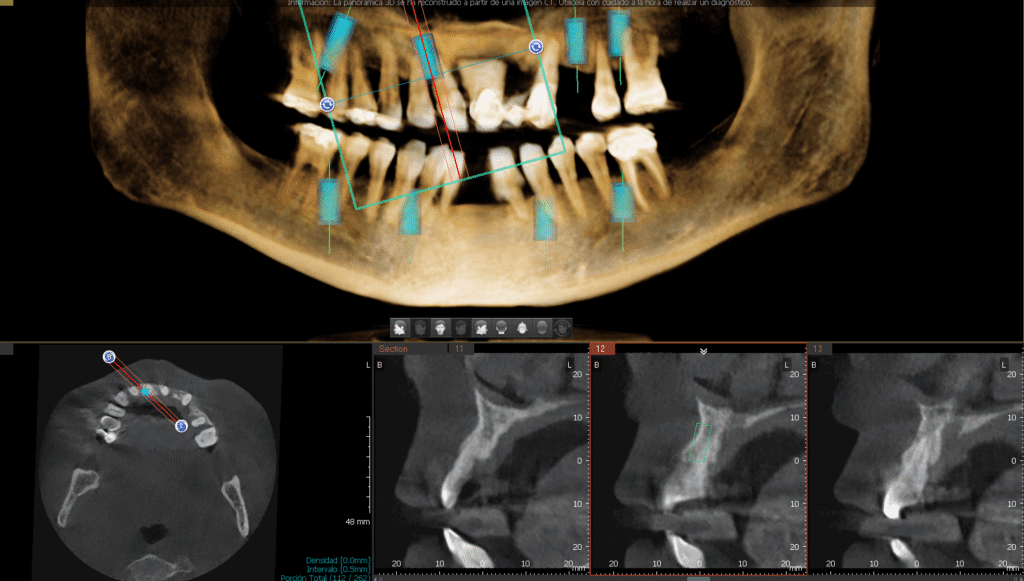

Mediante una tomografía computarizada, localizamos los sitios ideales para colocar los implantes. Incluso con poco hueso, podemos compensar la posición con aditamentos angulados. Sin embargo, en casos de atrofia maxilar severa, sí será necesario un injerto de hueso (bone graft). En este escenario, el tiempo de espera para colocar los implantes finales sería de 6 a 9 meses

Gracias a la planificación digital y la tomografía, decidimos cuántos necesitas para una rehabilitación bimaxilar (superior e inferior) estable y duradera.